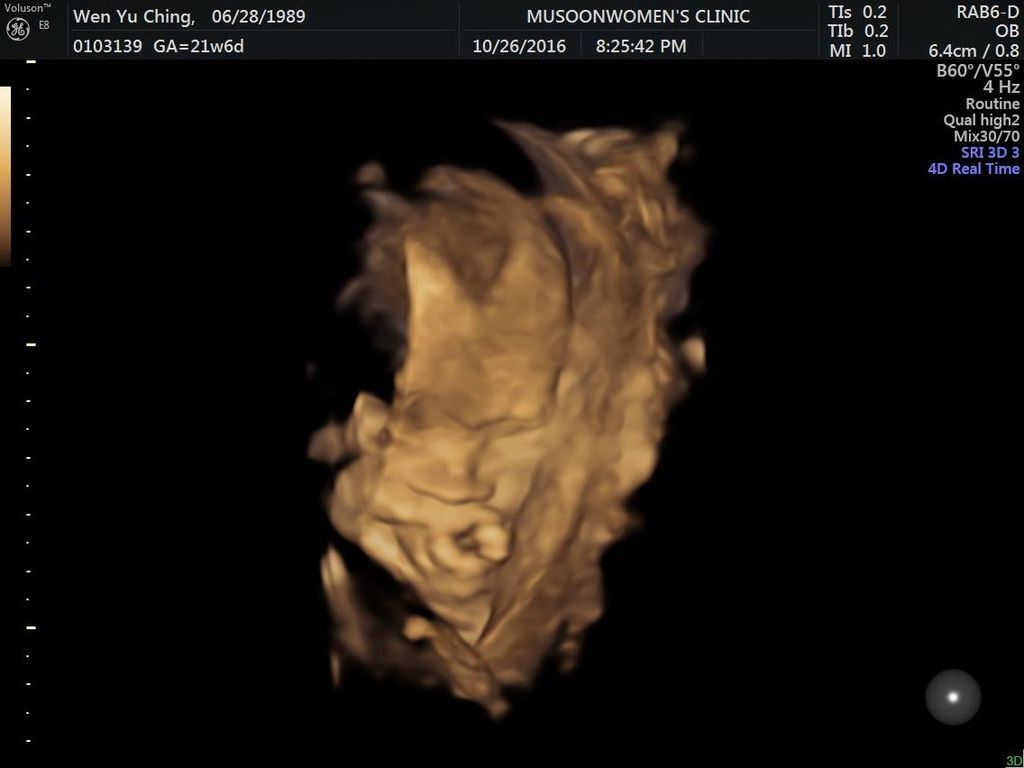

10.26_21w6d (3)

懷孕 (21-24W)高層次超音波: 左心室有一 顆小白點 嘖嘖